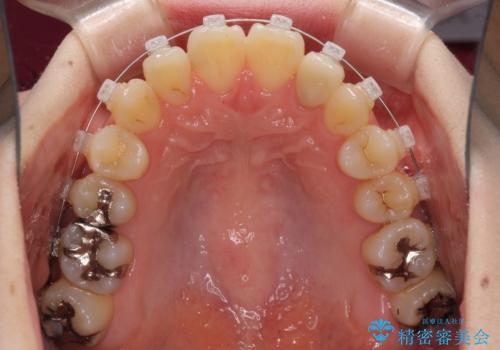

- 矯正装置

- クリアブラケット

- 治療期間

- 1年3ヶ月

- 下顎の歯が舌側に倒れていることと、前歯の咬み合わせの不具合を気にして来院された患者様です。

受け口傾向の口元であるため、下顎左右小臼歯各1歯を抜歯して歯列を整えることとしました。

前歯には治療中の仮歯が装着されていたため、矯正治療後にオールセラミッククラウンにて補綴治療を行うこととしました。